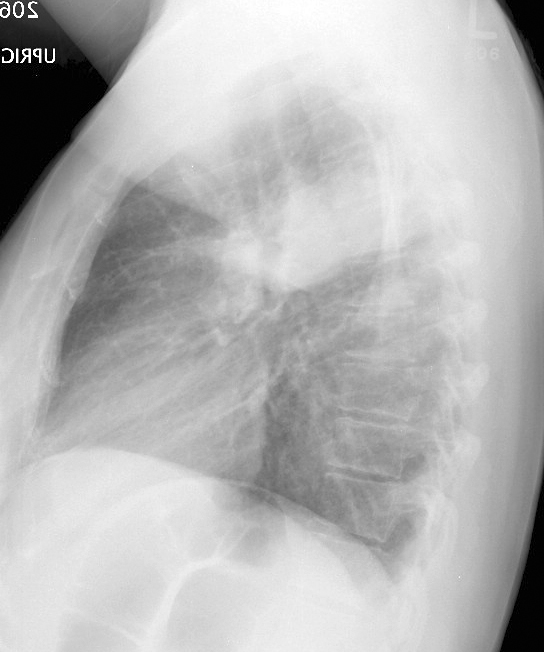

Gallery Pneumonia Case 7 RUL pneum Lat

Case 7 RUL pneum Lat